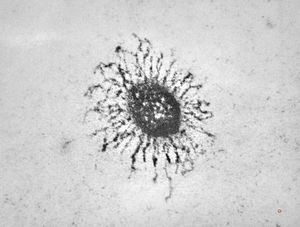

M,41y. | ribosome-lamella complex in tricholeukocyte -hairy cell leukemia, spleen

M,41y. | ribosome-lamella complex in tricholeukocyte -hairy cell leukemia, spleen

M,41y. | ribosome-lamella complex in tricholeukocyte -hairy cell leukemia, spleen